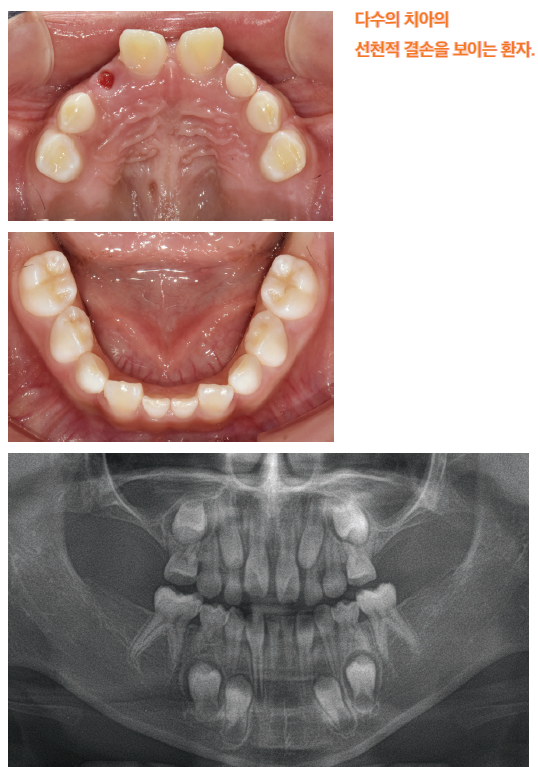

선천성 결손치란 태어날 때부터 영구치가 하나 이상 없는 상태를 의미하며, 사랑니(제3대구치)를 제외한 정상적인 28개의 영구치 가운데 일부 치아가 결손된 경우를 말합니다. 이는 치아의 발생 과정 중 치배 형성에 문제가 생겨 발생하게 됩니다. 결손된 치아의 수에 따라 일부 치아가 결손된 경우를 부분무치증(hypodontia), 6개 이상의 치아가 결손된 경우를 oligodontia, 그리고 모든 치아가 결손된 경우를 완전무치증(anodontia)으로 분류합니다. 이 중 oligodontia와 완전무치증은 비교적 드물게 나타납니다.

대한소아치과학회는 oligodontia와 anodontia를 치과적 희귀질환으로 분류하고 있으며, 이러한 환자들이 많지 않아 정확한 환자군 구축과 연구가 매우 필요합니다. 이에 이건희 소아암 희귀질환 재단의 지원을 받아 전국의 소아치과학교실 및 대학병원 연구진이 협력하여 발육장애성 희귀질환 코호트 구축 연구를 진행하고 있습니다. 본 연구에서는 결손치를 가진 환자들의 임상적 특성과 양상, 사회•경제적 부담 등을 조사하여, 향후 이들을 위한 제도적 지원 마련에 기여하고자 합니다.